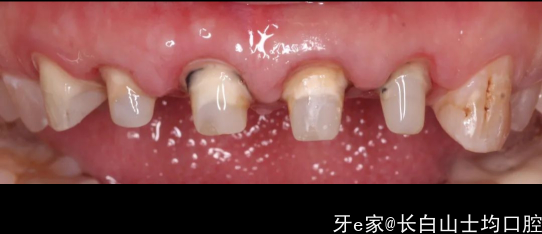

患者很难过,之前做的牙齿,大概有十年了,掉了,2-2联冠,检查之后发现几个问题:

1.患者四个残根,当时看片子(片子遗失)四个根的根管做的都不理想,需要重新做,然后打桩修复,方案定向简单,说干就干。2.针对第一个问题,和修复方案的确定,我们发现患者是一个深覆合,这里面就给最终修复的美学带来了难题,为啥说难题,之前的照片找不到了,但是有个石膏模型的照片。

3.我们能看到龈缘发黑,还有点肿,幸运的是患者的牙龈很厚,好像没太大炎症,但是探诊发现,之前备牙的肩台在龈下非常深的位置,这个就是医源性的问题了,不多说…